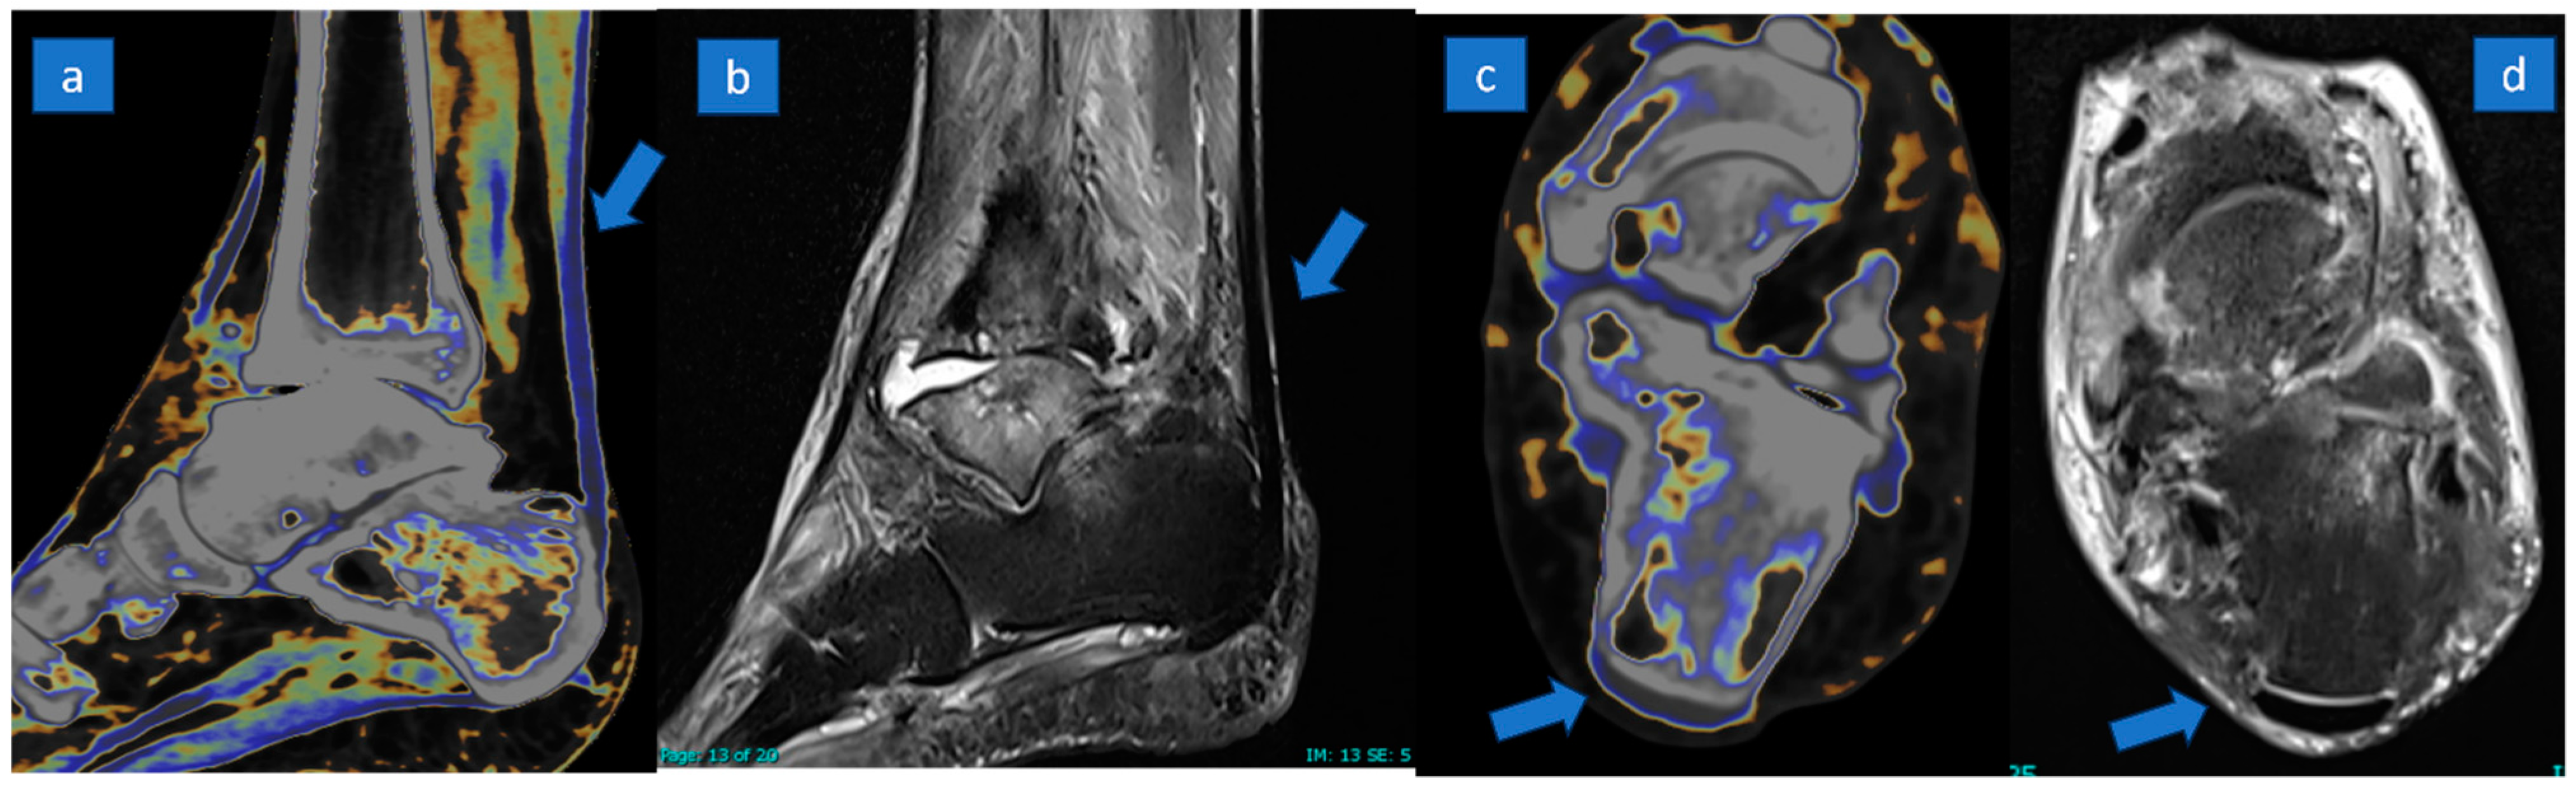

3.2. MRI Results

3.3. DECT Results